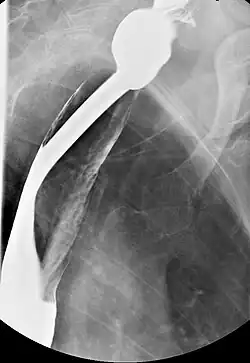

Barium esophagography and videofluoroscopy can aid in detecting esophageal webs. Esophagogastroduodenoscopy allows for the visual confirmation of these webs, which are caused by subepithelial fibrosis.

Right posterior oblique prone single contrast fluoroscopic image showing a circumferential thin cervical esophageal web.